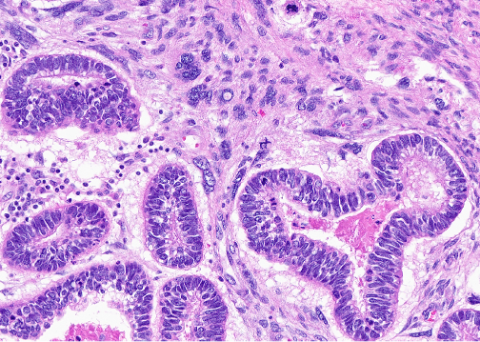

Figure 3. Medium power view of high-grade malignant stroma surrounding malignant high-grade glandular epithelium arranged in a biphasic pattern.

The stromal component above reflects a homologous undifferentiated sarcoma composed of polymorphous round to spindled cells with large vesicular nuclei, coarse chromatin, scant cytoplasm, and readily identifiable mitotic figures. The epithelial component above demonstrates serous carcinoma, however, can be composed of endometrioid, clear cell, or squamous carcinoma.